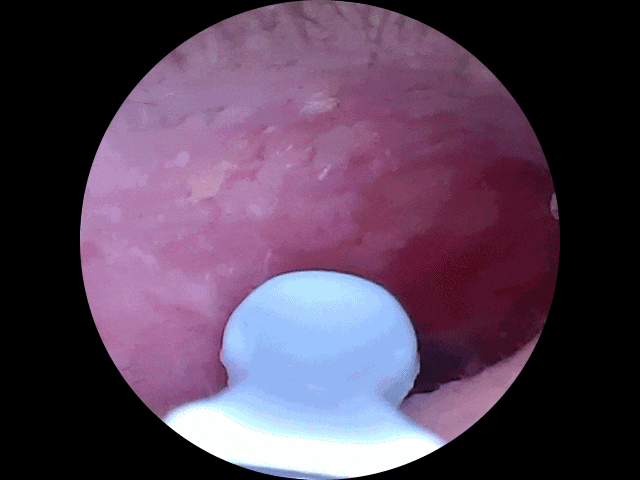

Step 2:耳道探险实录

●第一次把耳勺伸进耳朵时,我仿佛打开了新世界:震撼画面:屏幕上赫然出现一片“金色沙漠”(耳垢)+“黑色灌木丛”(耳毛),甚至能看到耳膜若隐若现(友情提示:别戳它!)。

●精准打击:用耳勺头轻轻一刮,耳垢像雪崩一样哗啦啦掉下来;顽固分子换金属镊子一夹,爽感堪比挤黑头。